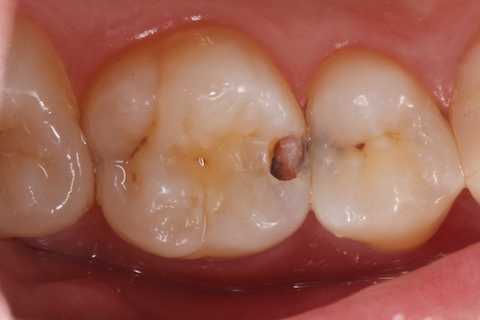

20代女性、右上6、咬合性外傷による隣接面カリエス

この歯は開ける前にエアーでしみていたのだが、開けるとしみなくなった。なんでですかね?

霧吹きの原理でエアスリットが狭い方が象牙細管内のリンパ液が吸い上げられやすいんでしょうね?

クラックが気になるのだが、象牙質には広がっていないようだったので、このまま充填した。

では時系列でどうぞ